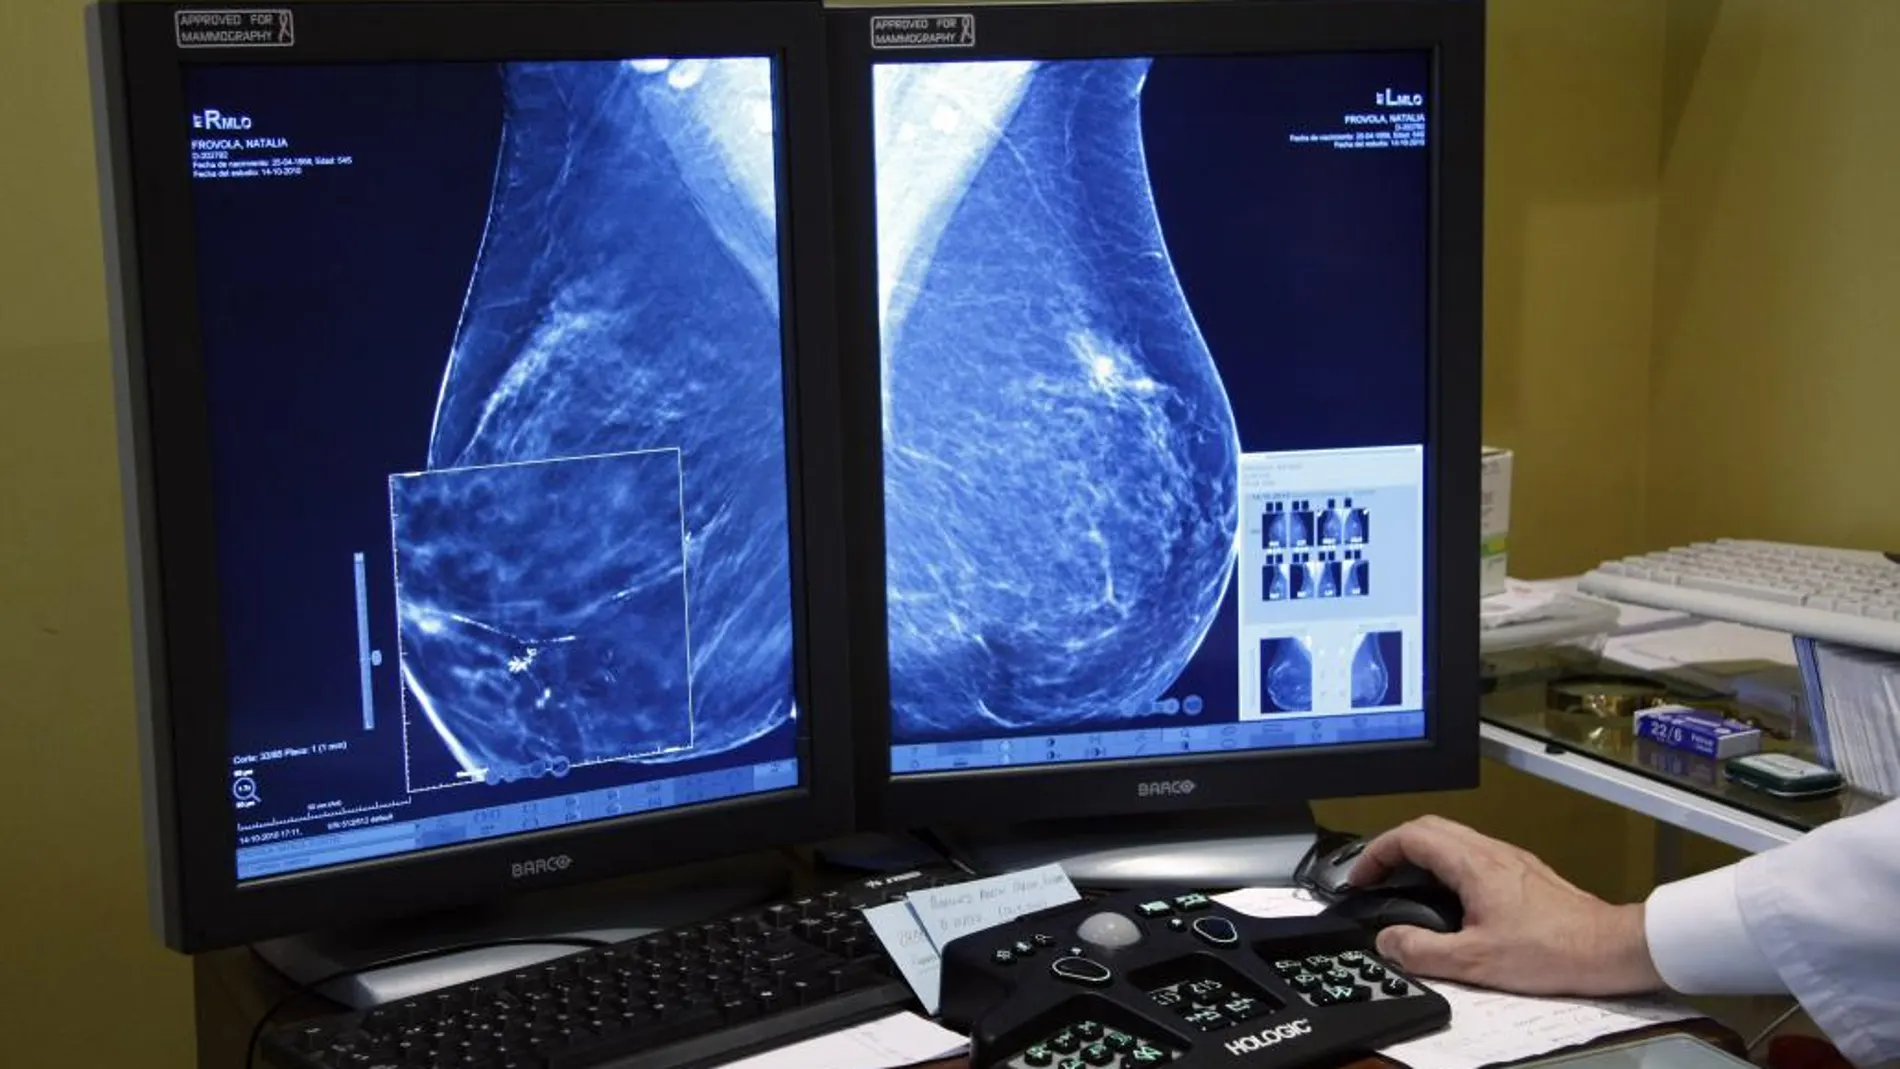

Igualmente, la portavoz de la comisión de seguimiento, constituida este pasado viernes, ha reiterado que en la doble lectura de una mamografía que realizan siempre dos radiólogos, "se adopta la actitud más agresiva", es decir, "se tiene en cuenta el diagnóstico más grave para aumentar así la detección y poner en marcha el seguimiento indicado por el facultativo". Gracias a este sistema de doble lectura independiente no consesuada se incrementa en hasta un 15% la detección de casos de cáncer de mama.

El consejero de Sanidad, Presidencia y Emergencias de la Junta de Andalucía, Antonio Sanz, ha informado este viernes de que se han identificado 2.317 mujeres del programa del cribado de cáncer de mama con hallazgos radiológicos clasificados como BI-RADS 3 ("probablemente benignos"), de las que en torno al 90% son del Hospital Universitario Virgen del Rocío de Sevilla, que habían superado el plazo recomendado por las guías clínicas para el seguimiento de esos hallazgos.

La Junta está procediendo a la revisión y actualización del proceso asistencial integrado de cáncer de mama, vigente desde 2011, con el fin de adaptarlo a los últimos avances científicos, tecnológicos y organizativos. Y, en paralelo, se incorporará progresivamente la inteligencia artificial al programa de cribado, una herramienta que ya ha demostrado buenos resultados en proyectos piloto desarrollados en Córdoba y que contribuirá a aumentar la precisión diagnóstica y la eficiencia del sistema.